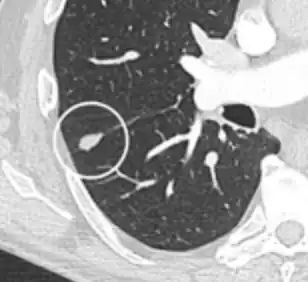

• A lung nodule abutting a pulmonary cyst is a rare finding, yet indicating cancer.[9]

• Bubble-like lucencies in the nodule indicate cancer:[9]